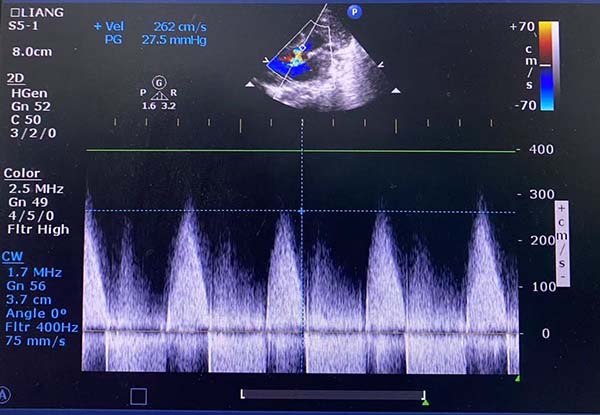

在医院特聘教授、上海交通大学医学院附属上海儿童医学中心李奋教授指导下,手术由韩波教授带领副主任医师姜殿东、伊迎春共同完成,心脏超声科主任医师梁皓全程提供床旁心脏超声监测。手术过程中,经股动脉置入8×40mm球囊导管行瓣膜成形,术后即刻跨瓣峰压差降至28mmHg,仅伴轻度主动脉瓣反流。整个操作无并发症发生,患儿术后症状显著缓解,48小时康复出院。

球囊扩张后超声测量跨瓣峰压差